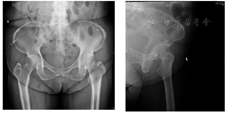

1.2013年5月双髋关节正侧位X线片显示左侧股骨颈骨折,GardenII型(图1)。

2.2015年12月双髋关节正侧位片显示左侧股骨颈骨折已愈合,发生颈吸收、颈短缩,空心钉退钉(图2)。